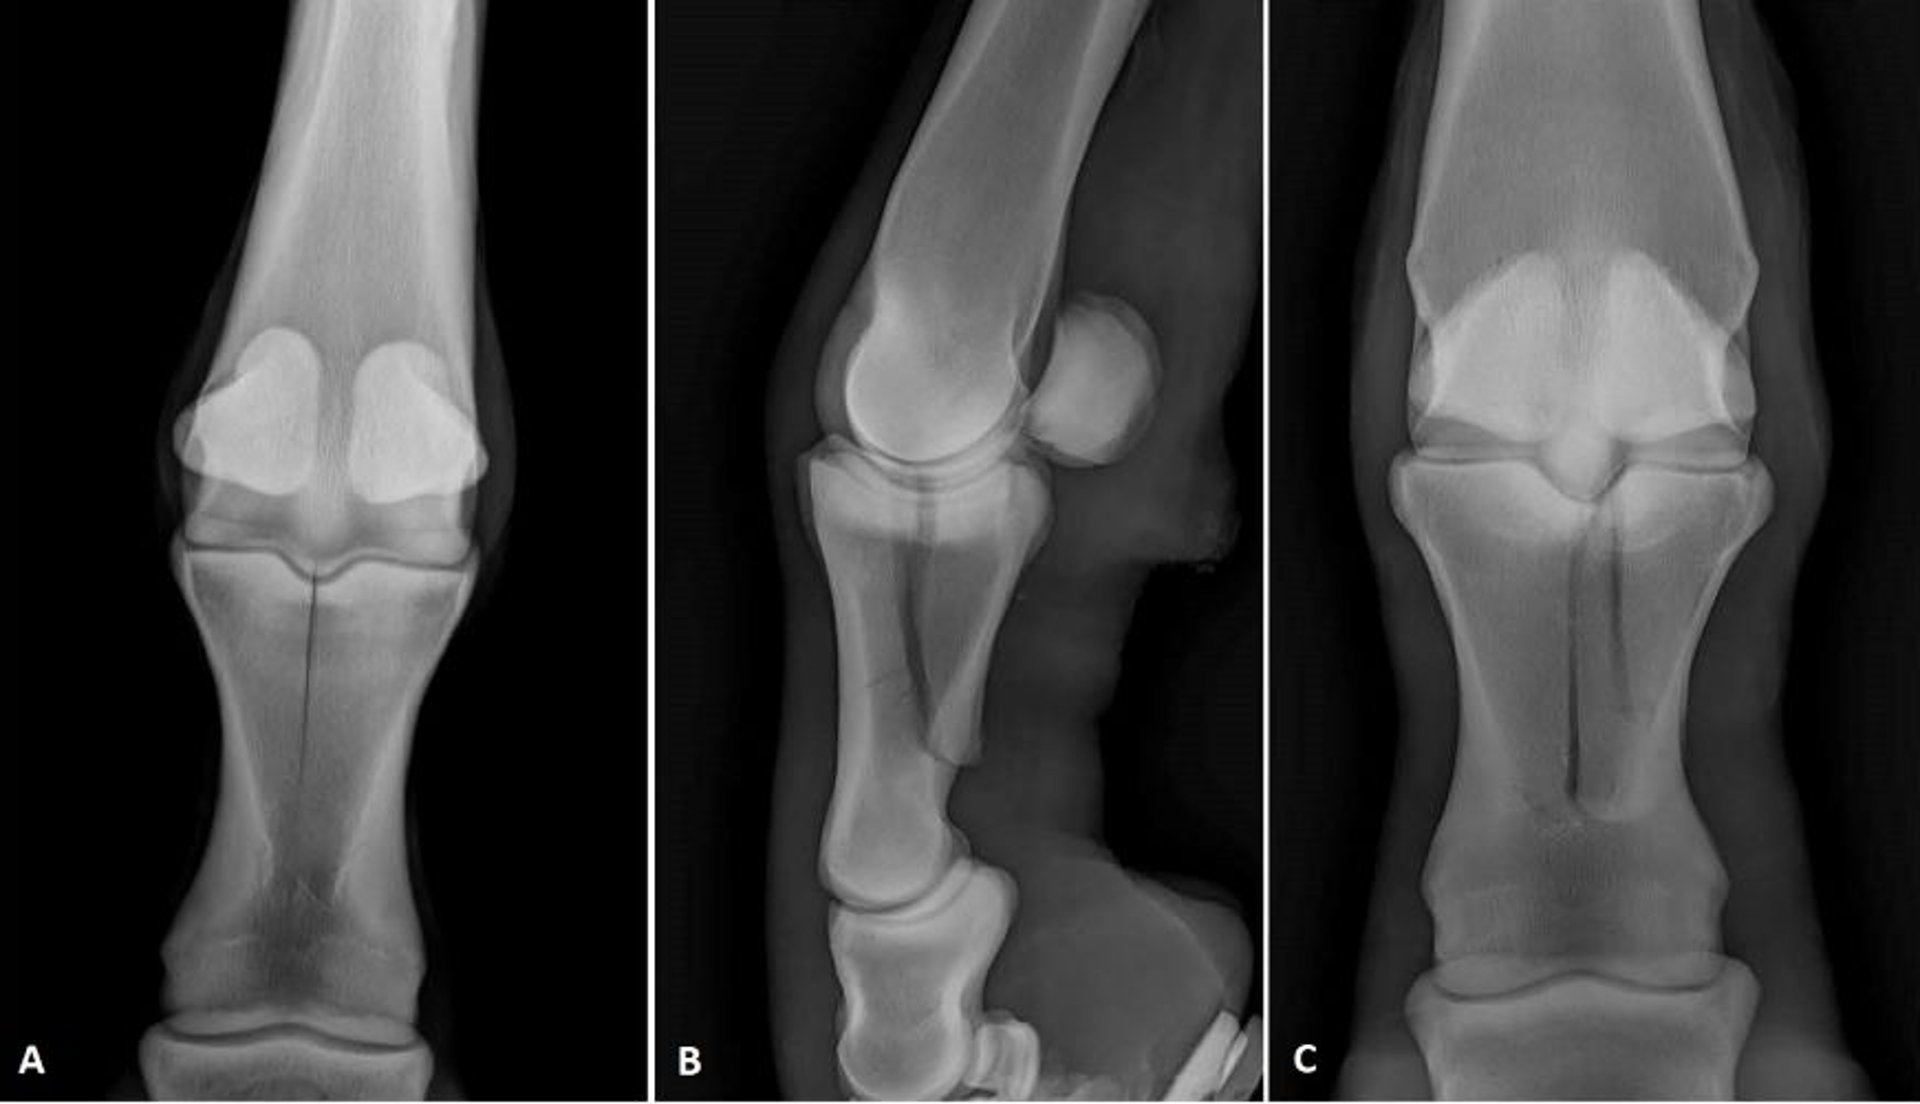

Imágenes radiográficas que muestran dos configuraciones diferentes de fracturas de la primera falange en caballos. (A) Vista dorsopalmar de una fractura sagital incompleta. (B) Vista lateral y (C) vista dorsopalmar de una fractura complicada.

Cortesía del Dr. Matthew T. Brokken.